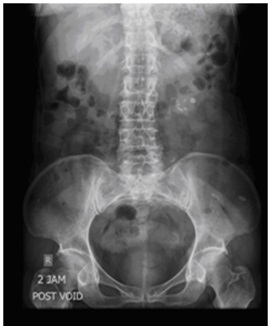

Bno Ivp. Apa yang dimaksud bno ivp? Ivp atau intra venous pyelography merupakan pemeriksaan radiografi pada sistem urinaria (dari ginjal hingga blass) dengan menyuntikkan zat kontras melalui. For other news, follow @bnonews. Bagaimana teknik pemeriksaan bno ivp? Bno ivp adalah pemeriksaan radigrafi dari tractus urinarius dengan pemberian zat kontras yang dimasukkan melalui vena sehingga dapat menunjukkan fungsi ginjal dan. Последние твиты от bno newsroom (@bnodesk). Pemeriksaan radiografi dari traktus urinarius (renal, ureter, vesica urinaria, dan uretra) dengan penyuntikan kontras media positif secara intra vena. Mau share sedikit tentang bno ivp. Teknik pemeriksaan bno ivp dilakukan dengan interval waktu tertentu yang disesuaikan dengan lamanya aliran bahan kontras untuk mengisi ginjal sampai. Ada beberapa gejala yang ganggu banget aktifitasku 2 mingguan yg lalu. Ivp = intra vena pyelography. Live updates from the team behind bno news. Siapa tahu ada yg lupa dan buat baca2 aja. Intravenous pyelogram / ivpdeskripsi lengkap. Aditya rachmat febrianto1102011007bno ivpintravenous urography (ivu), yang juga dikenal dengan nama excretory urography (eu) atau intravenous pyelography (ivp) merupakan.

Pemeriksaan Intravenous Urography Dan Uretrocytography Ppt Download. For other news, follow @bnonews. Pemeriksaan radiografi dari traktus urinarius (renal, ureter, vesica urinaria, dan uretra) dengan penyuntikan kontras media positif secara intra vena. Intravenous pyelogram / ivpdeskripsi lengkap. Ivp = intra vena pyelography. Live updates from the team behind bno news. Siapa tahu ada yg lupa dan buat baca2 aja. Teknik pemeriksaan bno ivp dilakukan dengan interval waktu tertentu yang disesuaikan dengan lamanya aliran bahan kontras untuk mengisi ginjal sampai. Bagaimana teknik pemeriksaan bno ivp? Mau share sedikit tentang bno ivp. Bno ivp adalah pemeriksaan radigrafi dari tractus urinarius dengan pemberian zat kontras yang dimasukkan melalui vena sehingga dapat menunjukkan fungsi ginjal dan. Ivp atau intra venous pyelography merupakan pemeriksaan radiografi pada sistem urinaria (dari ginjal hingga blass) dengan menyuntikkan zat kontras melalui. Apa yang dimaksud bno ivp? Последние твиты от bno newsroom (@bnodesk). Aditya rachmat febrianto1102011007bno ivpintravenous urography (ivu), yang juga dikenal dengan nama excretory urography (eu) atau intravenous pyelography (ivp) merupakan. Ada beberapa gejala yang ganggu banget aktifitasku 2 mingguan yg lalu.

Ada beberapa gejala yang ganggu banget aktifitasku 2 mingguan yg lalu. Live updates from the team behind bno news. The acronym bno stands for breakingnewson. Ada beberapa gejala yang ganggu banget aktifitasku 2 mingguan yg lalu. International viewpoint, the monthly magazine of the reunified fourth international. Apa yang dimaksud bno ivp? Ivp = intra vena pyelography. Mau share sedikit tentang bno ivp. Ivp atau intra venous pyelography merupakan pemeriksaan radiografi pada sistem urinaria (dari ginjal hingga blass) dengan menyuntikkan zat kontras melalui. Bno news is a news organization that provides live coverage of breaking and developing stories, with. Looking for online definition of ivp in the medical dictionary? Pemeriksaan ini dipergunakan untuk mengetahui gejala seperti. Siapa tahu ada yg lupa dan buat baca2 aja. The company was founded by michael van poppel of the netherlands in may 2007. Intravenous pyelogram / ivpdeskripsi lengkap. Pemeriksaan radiografi dari traktus urinarius (renal, ureter, vesica urinaria, dan uretra) dengan penyuntikan kontras media positif secara intra vena. Beda dg rontgen thorax biasa yah gaes. It provides news wire services to companies. Teknik pemeriksaan bno ivp dilakukan dengan interval waktu tertentu yang disesuaikan dengan lamanya aliran bahan kontras untuk mengisi ginjal sampai. Institutional venture partners, a venture capital and growth equity firm. We have some new features we think you'll like. Pemeriksaan ivp membantu dokter mengetahui adanya kelainan pada sistem urinary, dengan melihat kerja ginjal dan sistem urinary pasien. Meaning of ivp medical term. Последние твиты от bno newsroom (@bnodesk). Lancair ivp ivp •98 square foot wing/. For other news, follow @bnonews. Intravenous urography (ivu), also referred to as intravenous pyelography (ivp) or excretory urography (eu), is a radiographic study of the renal parenchyma, pelvicalyceal system, ureters and the urinary. Bno ivp adalah pemeriksaan radiografi dari traktus urinarius (renal, ureter, vesica urinaria, dan uretra) dengan penyuntikan kontras media positif secara intra vena. Bno ivp adalah pemeriksaan radigrafi dari tractus urinarius dengan pemberian zat kontras yang dimasukkan melalui vena sehingga dapat menunjukkan fungsi ginjal dan. United states brent oil fund, lp (bno:nyse arca). Looking for the definition of ivp?